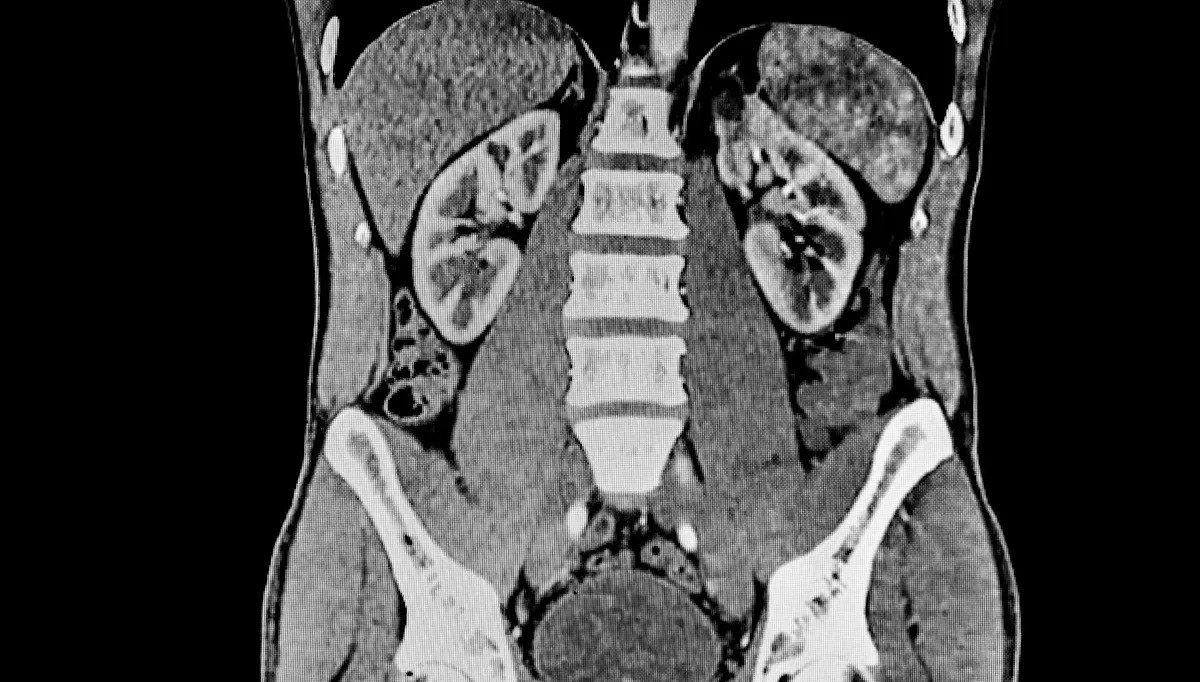

It has also been discovered that the physical and chemical properties of polyamide affect how it is distributed in the body after ingestion, with microplastics accumulating in organs such as the liver.